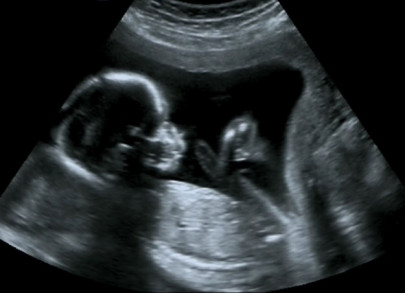

Family planning: Abortion rates going up as only 31% people use contraceptives

Speakers say around 70% of couples not using anything to prevent unwanted pregnancies